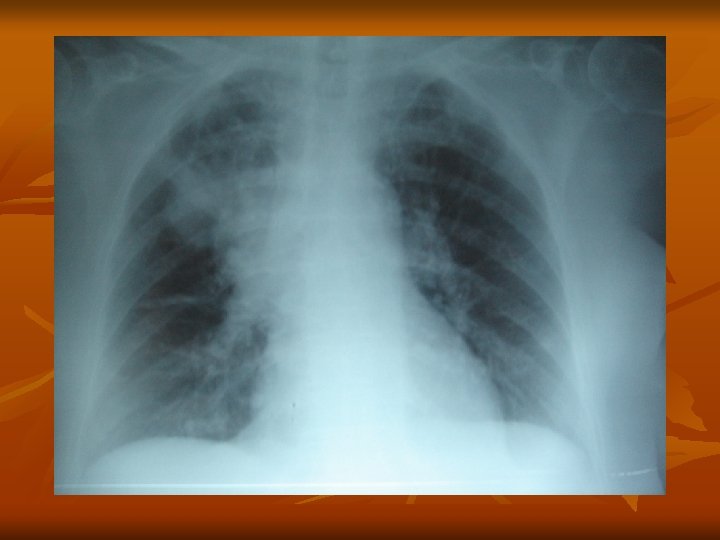

n Diagnóstico imagenologico: n 1. - Radiografia de Torax n 2. - TAC de Torax ( diag. Diferencial)